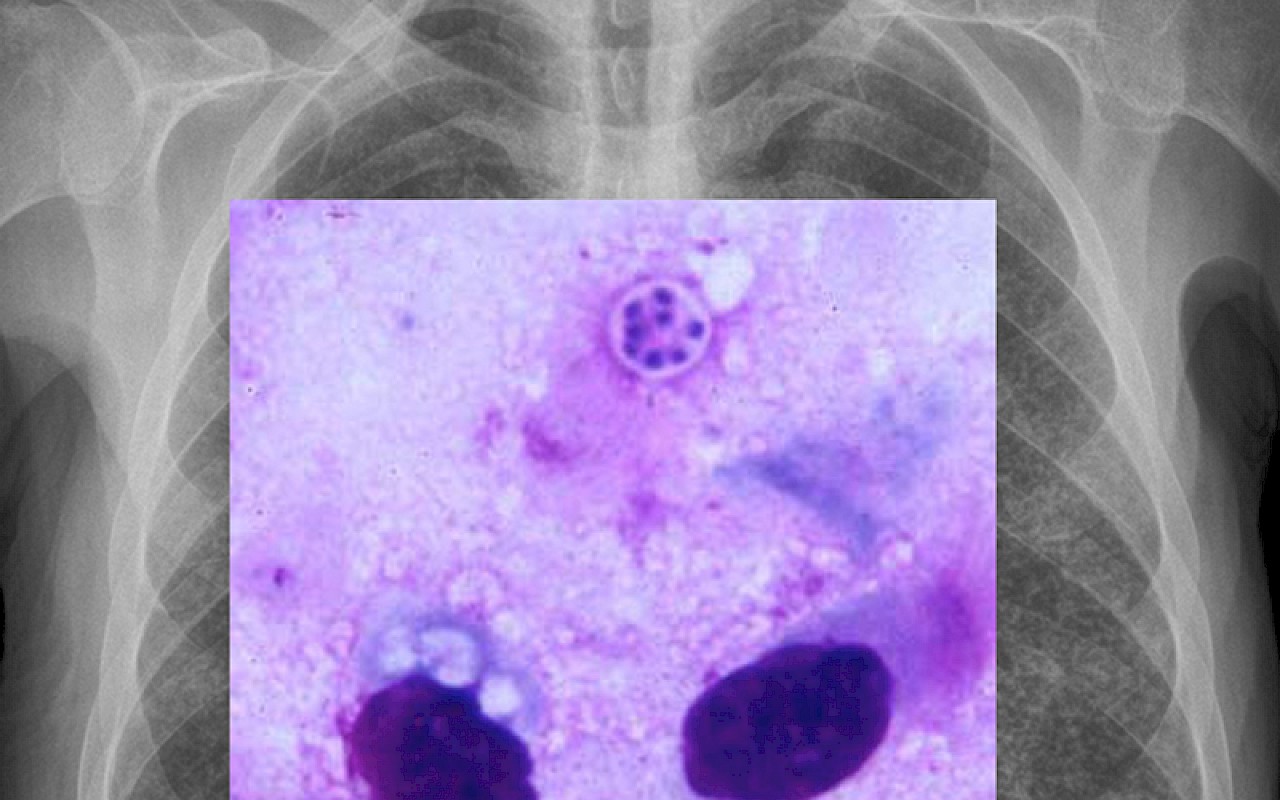

Back to the future — Tuberkuloseforschung im Kontext einer HIV-Infektion in Uganda

Dr. med. J. Fehr ist ausgewiesener Spezialist für Infektionskrankheiten und arbeitet als Oberarzt am Universitätsspital Zürich. Seine Forschung konzentriert sich auf Fragen aus dem klinischen Alltag in Entwicklungsländern. Jan Fehr leitete Forschungsprojekte in Tanzania und trägt die Verantwortung beim Aufbau einer Forschungskooperation mit der Makerere Universität in Kampala, Uganda. Im Mittelpunkt steht bei diesem Projekt die Verbesserung der Therapie von Patienten, welche an einer Tuberkulose und gleichzeitig an einer HIV-Infektion leiden. Tuberkulose ist zur Zeit die Haupttodesursache von HIV-Patienten, welche in den ärmsten Gebieten Afrikas leben. Das Problem ist, dass momentan kaum neue, Tuberkulosemedikamente in Aussicht sind. Gefordert sind Strategien, die herkömmlichen Medikamente optimal einzusetzen. Genau hier setzt das aktuelle Forschungsprojekt in Uganda an. Das primäre Ziel ist es, die optimale Dosierung dieser ‚alten’ Medikamente zu eruieren, um Therapieversagen verhindern zu können. Gefragt sind Visualisierung in zwei Bereichen: Von grossem Nutzen wäre die Visualisierung der Wirkmechanismen der Medikamente auf molekularer Ebene. Im Weiteren besteht grosser Bedarf an Visualisierung auf Ebene Krankheitsverständnis und -bedeutung für den Einsatz im Entwicklungsland. Unter Berücksichtigung des entsprechenden kulturellen Hintergrunds sind Vorgänge der Krankheitsentwicklung, aber auch möglicher Diagnostik und Therapie zu vermitteln, was sowohl dem individuellen Patienten als auch einem breiteren Publikum ohne medizinische Ausbildung zu Gute kommt. Bei beiden Ansätzen geht es darum eine ‚alte’ Krankheit – Tuberkulose – welche im Kontext der Immunschwäche-Kranheit HIV enorm an Aktualität gewonnen hat, visuell zu vermitteln: Back to the future.